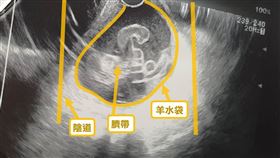

媽媽們要小心 臍帶脫垂恐釀1屍2命

「臍帶脫垂」指的是羊膜破裂後,臍帶滑落到子宮頸口、陰...